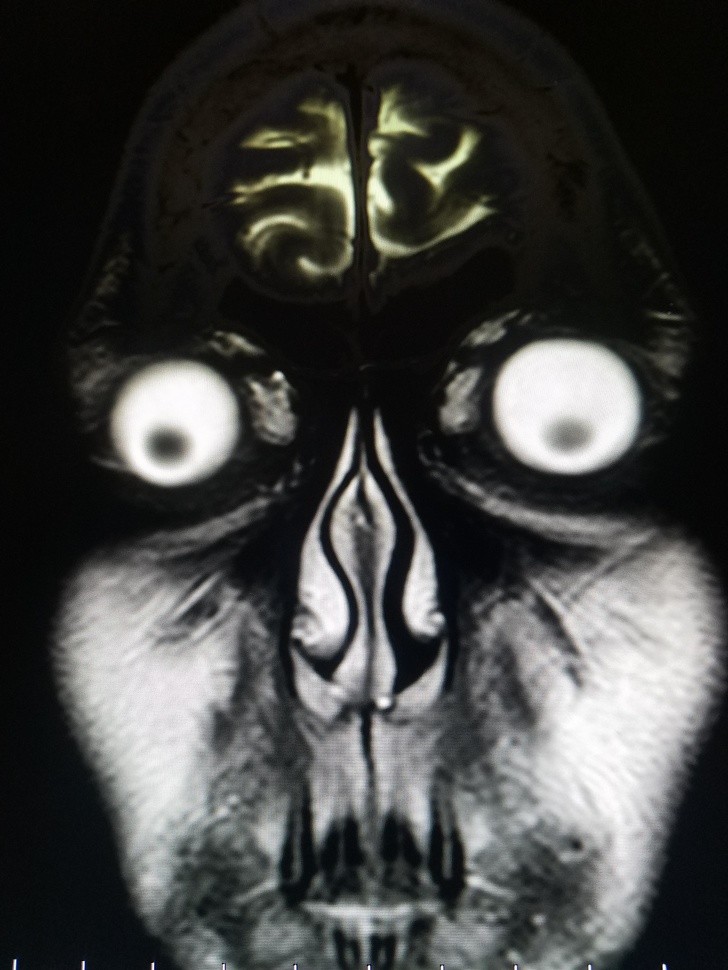

Ludzie to naprawdę dziwne stworzenia i mogą nam się przytrafiać niewiarygodnie dziwne rzeczy. Te prześwietlenia rentgenowskie zszokują nawet tych, którym wydaje się, że widzieli już wszystko.

Radiologi so tako že precej navajeni, da na rentgenskih posnetkih vidijo čudne stvari in nekatere izmed teh, ki smo jih za vas zbrali v galeriji, jih sploh niso presenetile. Tukaj je 15+ odštekanih in na trenutke šokantnih rentgenskih posnetkov.